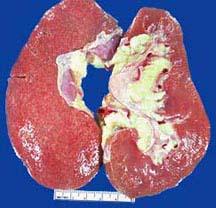

选项 A、结节性肾小球硬化症,具高度特异性 B、移植到糖尿病病人的正常肾脏发生糖尿病肾病的病理变化 C、糖尿病肾病引起的蛋白尿随着进行性肾功能衰竭而减少 D、1型糖尿病病人常死于肾功能衰竭 E、弥漫性肾小球硬化症最常见,但特异性低

答案 ABDE